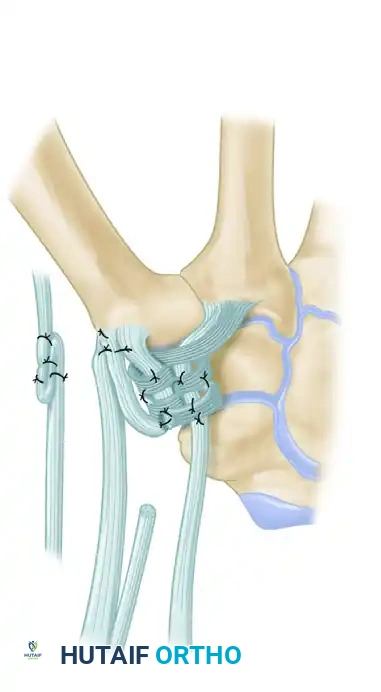

Figure: Schema of volar and radial ligament reconstruction. The complex course of the tendon strip creates robust reinforcement in the volar, dorsal, and radial aspects of the joint.

Intraoperative view of the final tendon weave and capsular reinforcement.